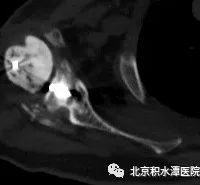

首先行假体取出、扩创控制感染,后期再行反肩关节置换。完善相关检查后,于2018年5月手术,扩创取出原假体,抗生素骨水泥植入。术中最大的难点在于肱骨侧假体、骨水泥及髓腔塞取出困难,而任何残留都可能会造成感染复发,术中采用肱骨干纵行劈开方式将假体、骨水泥和髓腔塞全部取出,并用钢丝捆扎修复,而肩胛盂侧的假体取出则较为顺利,但患者大小结节均已移位,肩袖组织完全挛缩。术后培养为表皮葡萄球菌,通过抗生素治疗,患者的感染顺利控制。